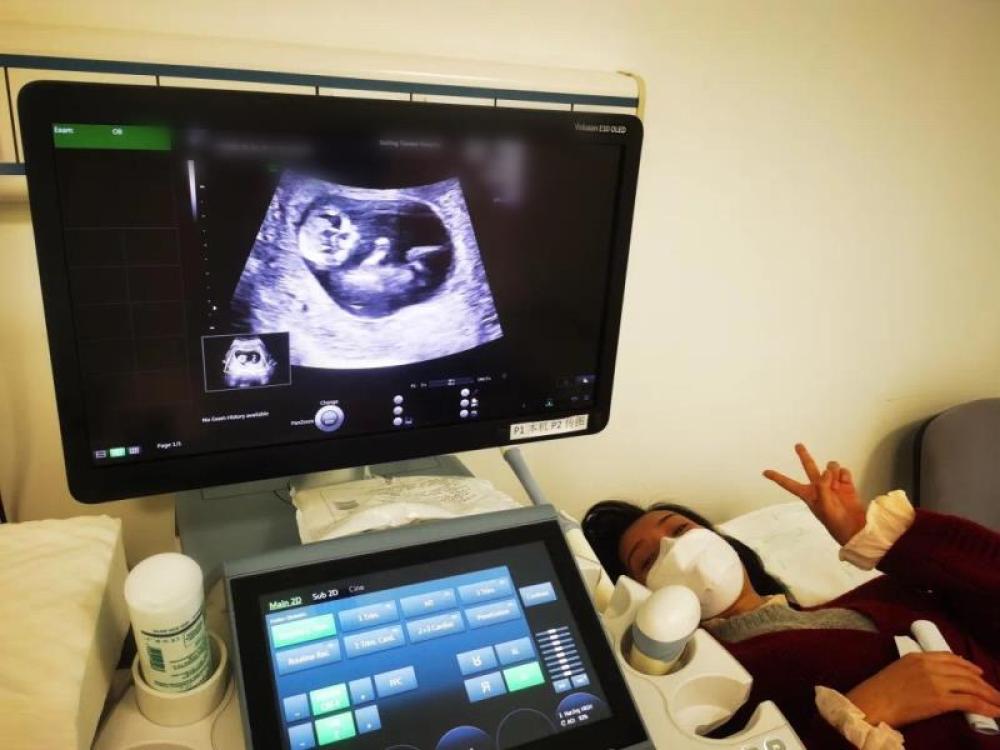

今天一早,妻子去醫(yī)院進(jìn)行B超檢查,同事用手機(jī)拍攝下了B超顯示屏上的畫(huà)面,記錄下了這個(gè)87天的小家伙第一次“亮相”。

圖為北京天壇醫(yī)院袁磊愛(ài)人做B超檢查。

“袁磊,看看你們家寶寶,可愛(ài)嗎?”收到同事發(fā)來(lái)的視頻,第一眼就看哭了,身邊的同事看完視頻也哭了。

視頻里,這個(gè)小家伙好像聽(tīng)到了外面的召喚,在媽媽的肚子里伸手、踢腿、翻身,用各種動(dòng)作進(jìn)行回應(yīng)……看到他那小胳膊小腿,一種從未有過(guò)的幸福感不停地向上涌,眼淚怎么也控制不住。

其實(shí)在武漢這么多天,他一直就是我的牽掛,今天終于看到他了,那種感受真是又緊張又激動(dòng),雖然還看不清他的樣子,但是已經(jīng)感受到他的活力。